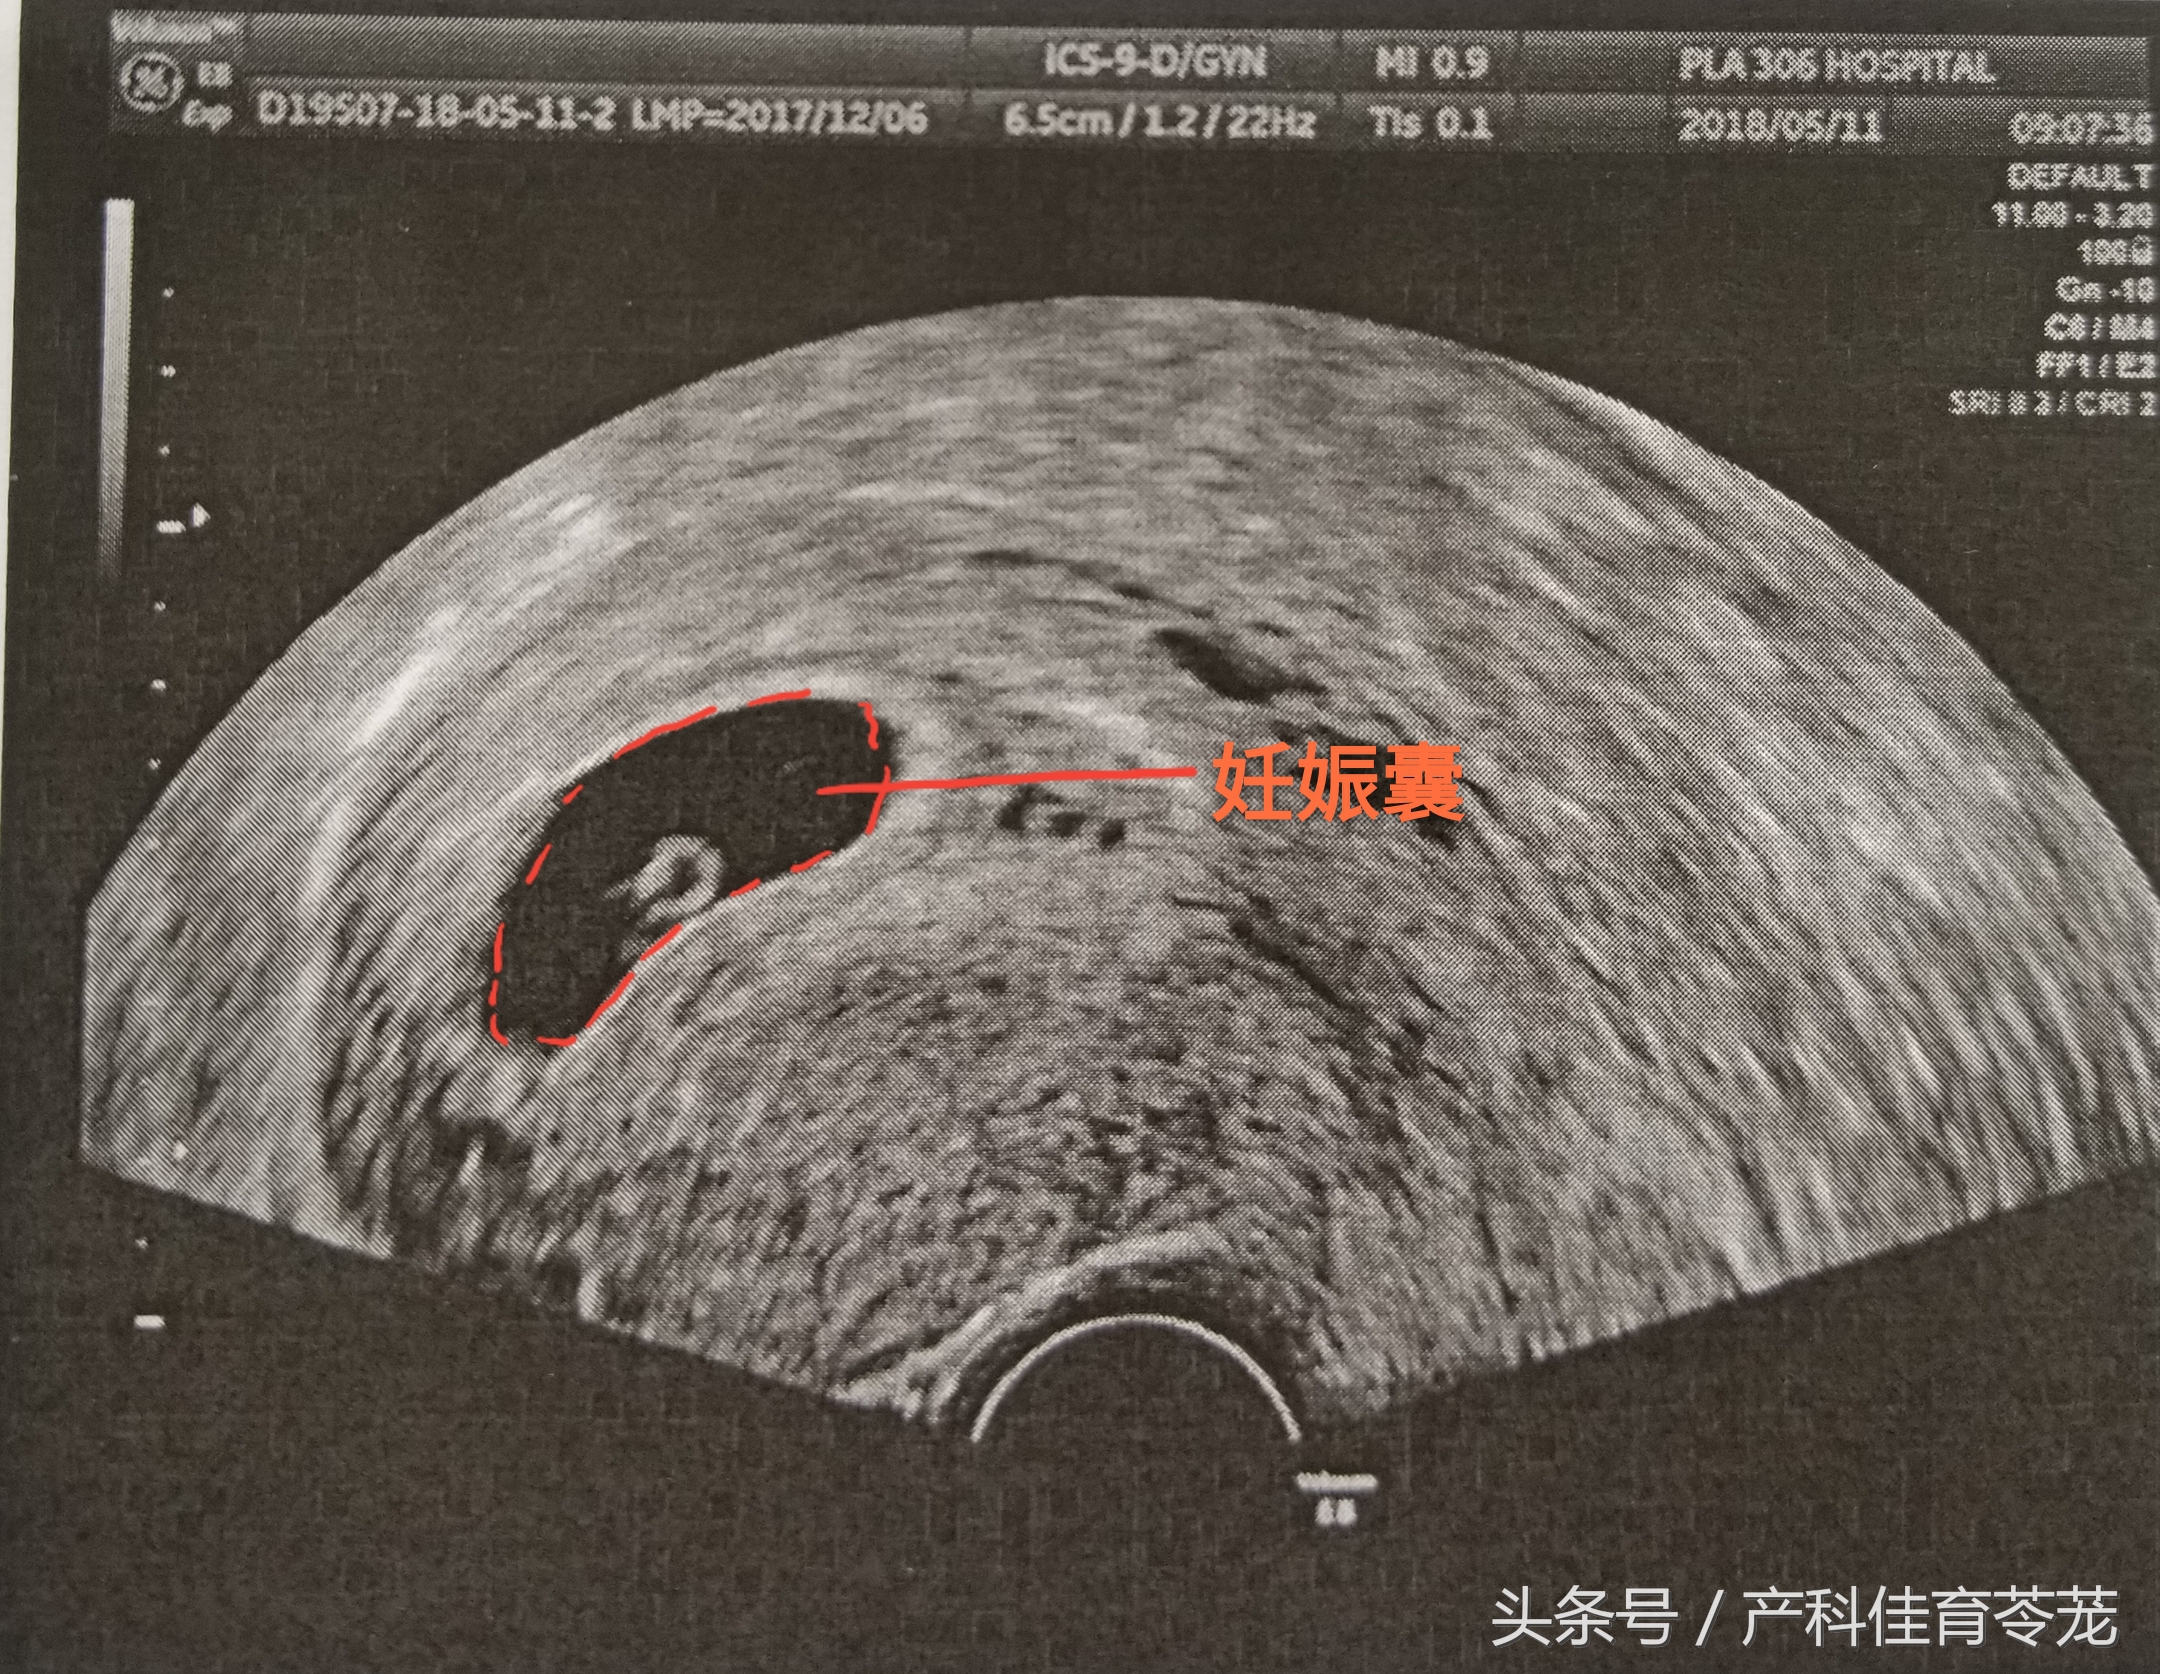

一、妊娠囊/胎囊(Gestational Sac GS)

GS 是围绕胚胎的结构,是超声最先看到的妊娠结构。

经腹超声(憋尿做的),在停经后5-6周可以看到,经阴道超声,在停经后4周就能看到。一般会测量GS的三个径线,所以您会看到“...X....X....cm/mm”的数值。

根据这些数值,可以用来确定妊娠时间:

妊娠天数=妊娠囊平均内径(mm)+30

妊娠周数=妊娠囊最大内径(cm)+3

注意:GS形态变异较大,根据它的测量值来推算孕龄的准确性较差。